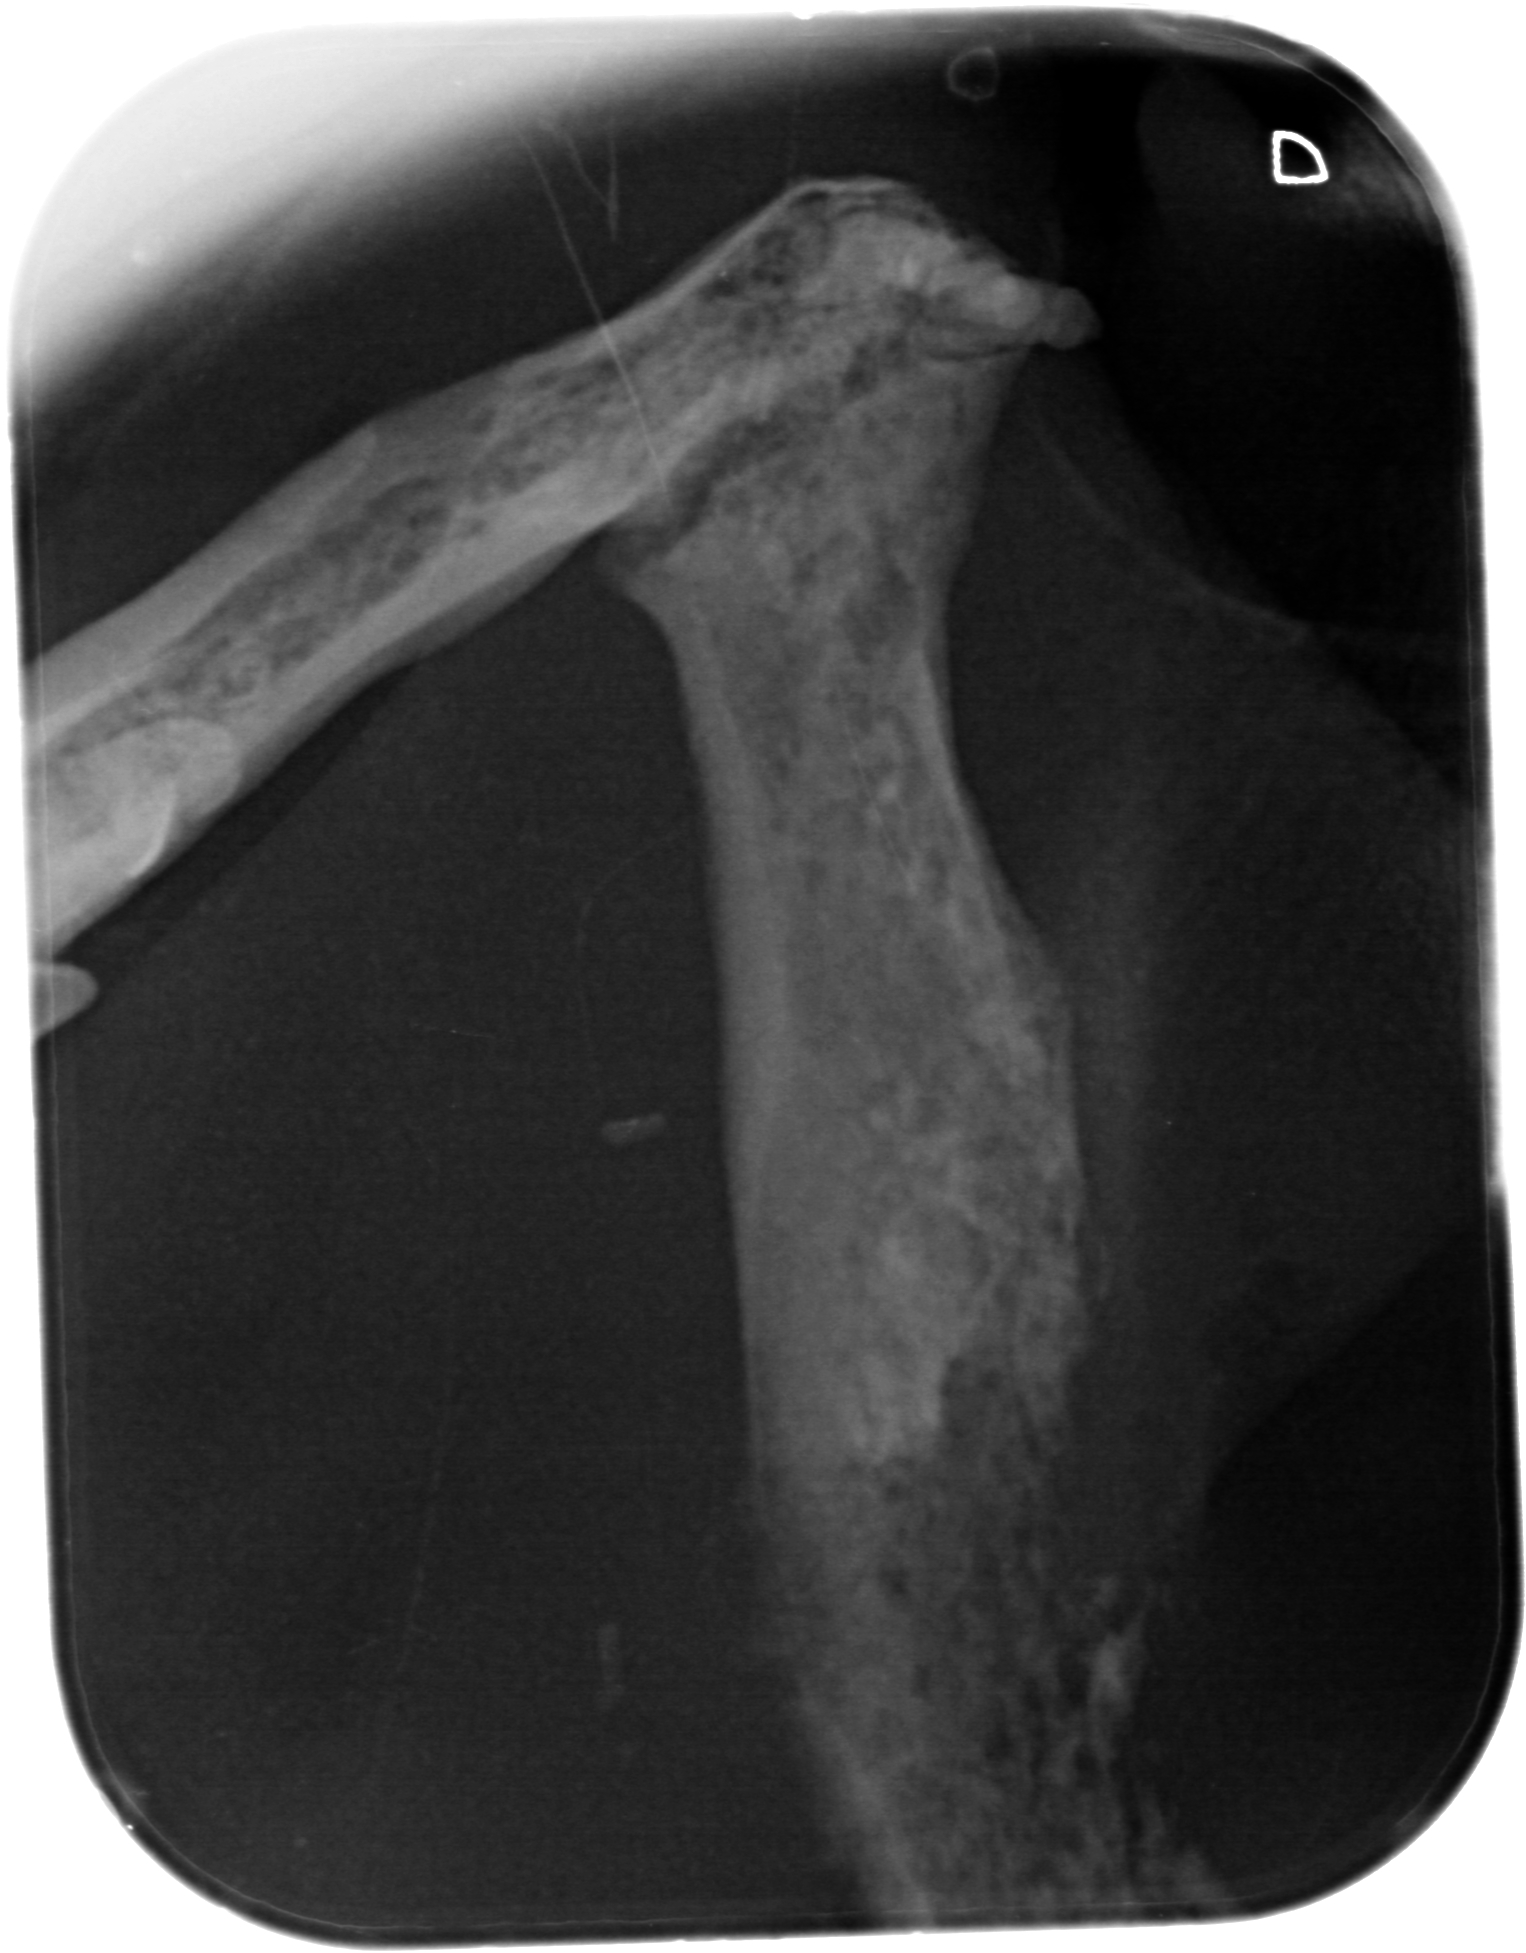

Kæbekræft hos Shana-Mio, 4, 24. januar 2013

Fuld størrelse er

1526 × 1953

pixel

Kæbekræft hos Shana-Mio, 3, 24. januar 2013